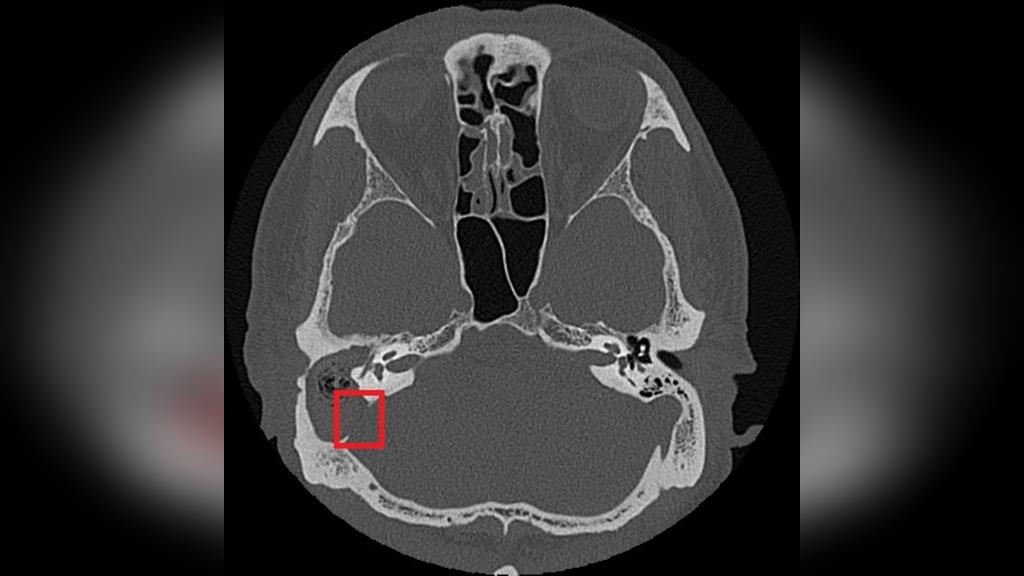

75歲的張先生右耳曾罹患慢性中耳炎並合併耳聾。近日右耳出現耳痛、耳脹並伴隨膿性分泌物,原先於診所治療未見改善,經檢查發現外耳道嚴重紅腫狹窄,內部堆積大量碎屑及膿液。慈濟醫院耳鼻喉科醫師鄭靜雯在進行局部清理及藥物治療後,症狀仍未明顯改善,後續更出現右側顏面神經麻痺。經顳骨電腦斷層檢查確認為慢性中耳炎併發膽脂瘤,且病灶已侵蝕顱底骨質,需安排住院治療。

由於膽脂瘤多發生在中耳或接近顱底的位置,一旦形成,可能影響聽力與神經功能,其分泌物亦容易滋生細菌,導致反覆感染;若未及時治療,可能引發暈眩,甚至因鄰近顱內而造成腦膜炎、腦炎或腦膿瘍。目前,手術切除是膽脂瘤根治的唯一方法,術前需以顳骨電腦斷層檢查評估膽脂瘤範圍及侵蝕程度;手術方式依病灶大小、位置,可能採耳內微創、耳前或耳後切開術,徹底清除膽脂瘤並重建受損結構。

急性發炎期則需輔以抗生素控制感染,術後追蹤可降低復發風險,但膽脂瘤若已侵蝕骨質,仍需長期觀察。以張先生為例,雖前後接受過局部藥物、抗生素治療,但考量其慢性中耳炎併發膽脂瘤已破壞聽小骨、乳突及部分顱底骨質,因此需從耳後切開進入外耳道及中耳腔,打開耳後的乳突骨,將病變組織除去後,重建修復骨骼和軟組織缺口。